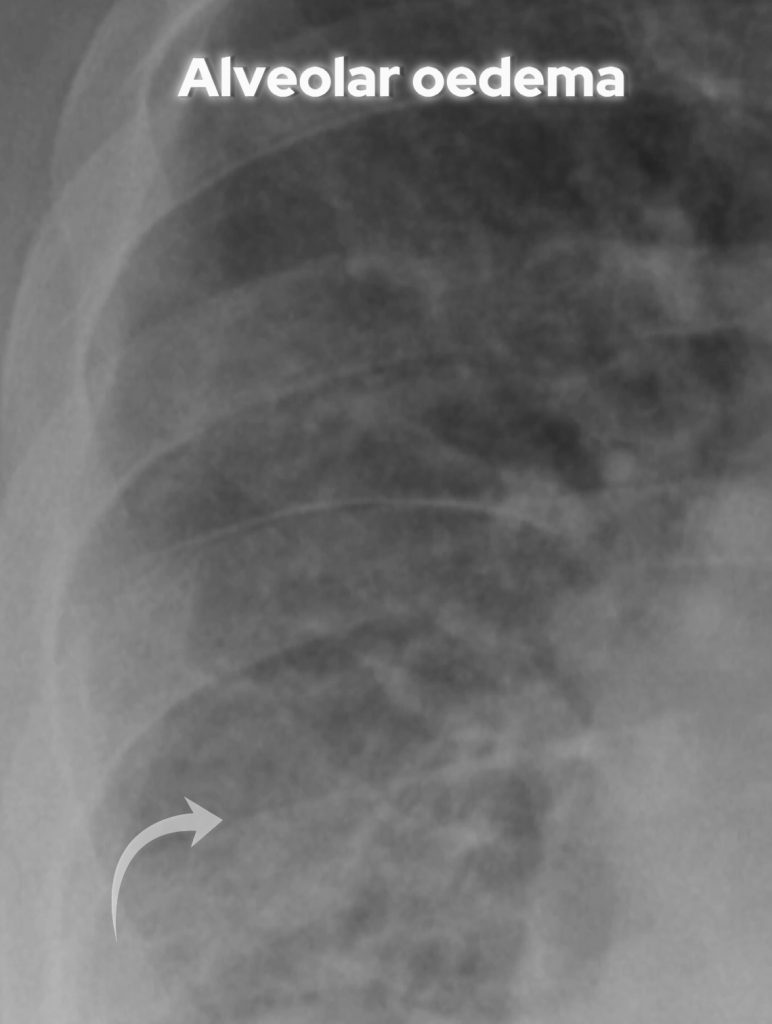

Alveolar Oedema:

• Fluid leaks into alveoli, causing fluffy opacities with air bronchograms.

• Rapid fluid accumulation can produce a bat wing pattern, central and bilateral.

Look for ‘fluffy’ alveolar oedema